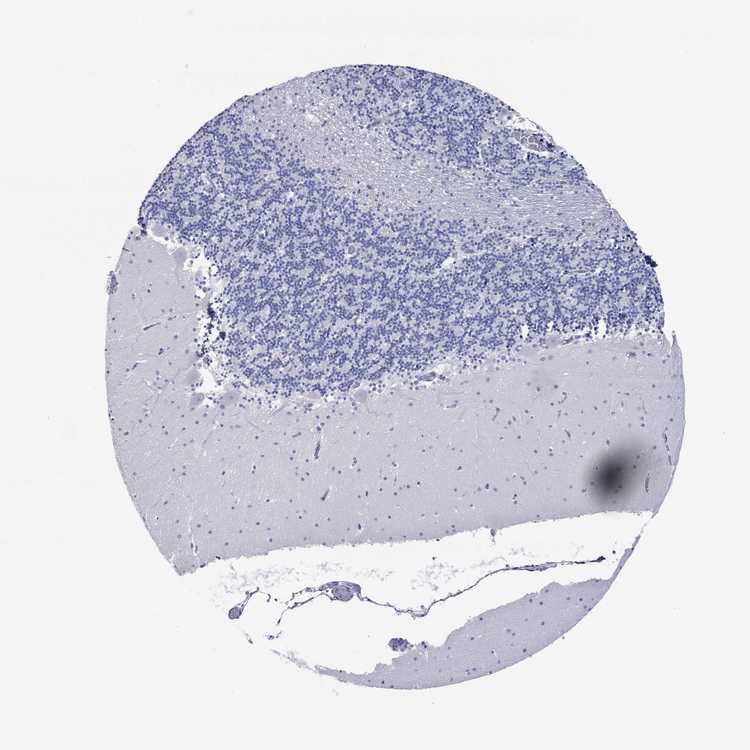

BRAIN CEREBELLUM Show tissue menu

CEREBELLUM - Expression summary

CEREBELLUM - Antibody stainingi

Antibody staining in the annotated cell types in the current human tissue is reported as not detected, low, medium, or high, based on conventional immunohistochemistry profiling in selected tissues. This score is based on the combination of the staining intensity and fraction of stained cells.

Each image is clickable and will lead to virtual microscopy that enables deeper exploration of all samples and also displays staining intensity scores, fraction scores and subcellular localization as well as patient and tissue information for each sample.

Antibody HPA074751

Purkinje cells Not detected

Cells in granular layer Not detected

Cells in molecular layer Not detected